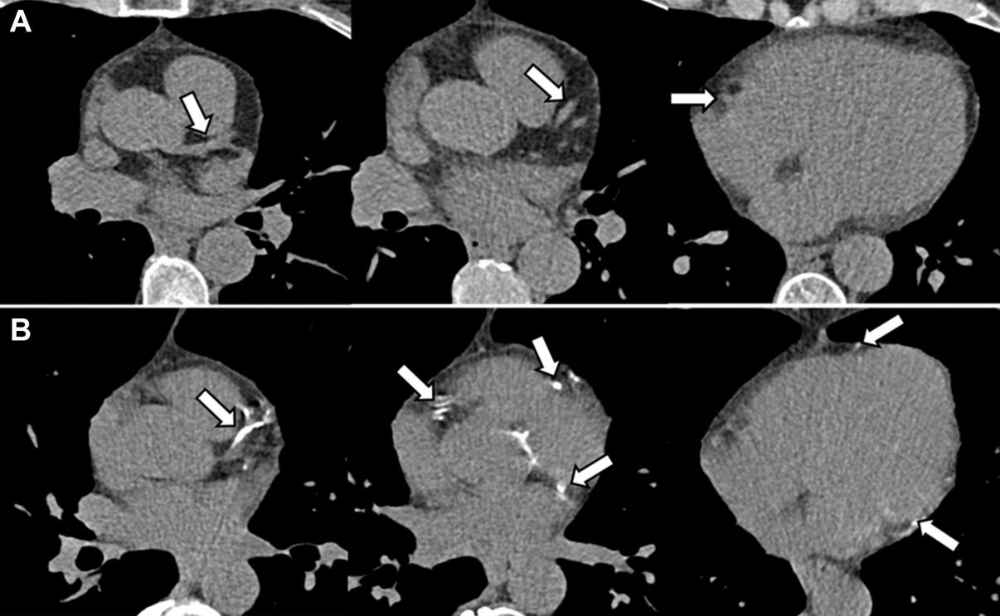

图片

图1:展示了CACS的计算方法,以及低风险和高风险CACS患者的示例

由于CACS为>3时MACE发生率更高,故将CACS分为两类:低(0-3)和中度至重度(4-12)。以心血管风险评分≥10%或冠状动脉钙化积分>3为界值,将患者分为4组: